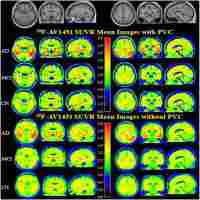

Applications of amyloid, tau, and neuroinflammation PET imaging to Alzheimer's disease and mild cognitive impairment